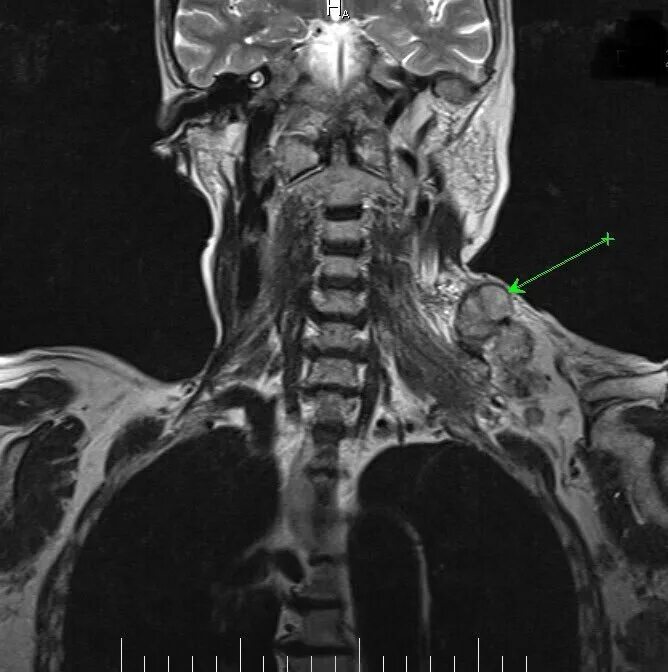

Кт тканей